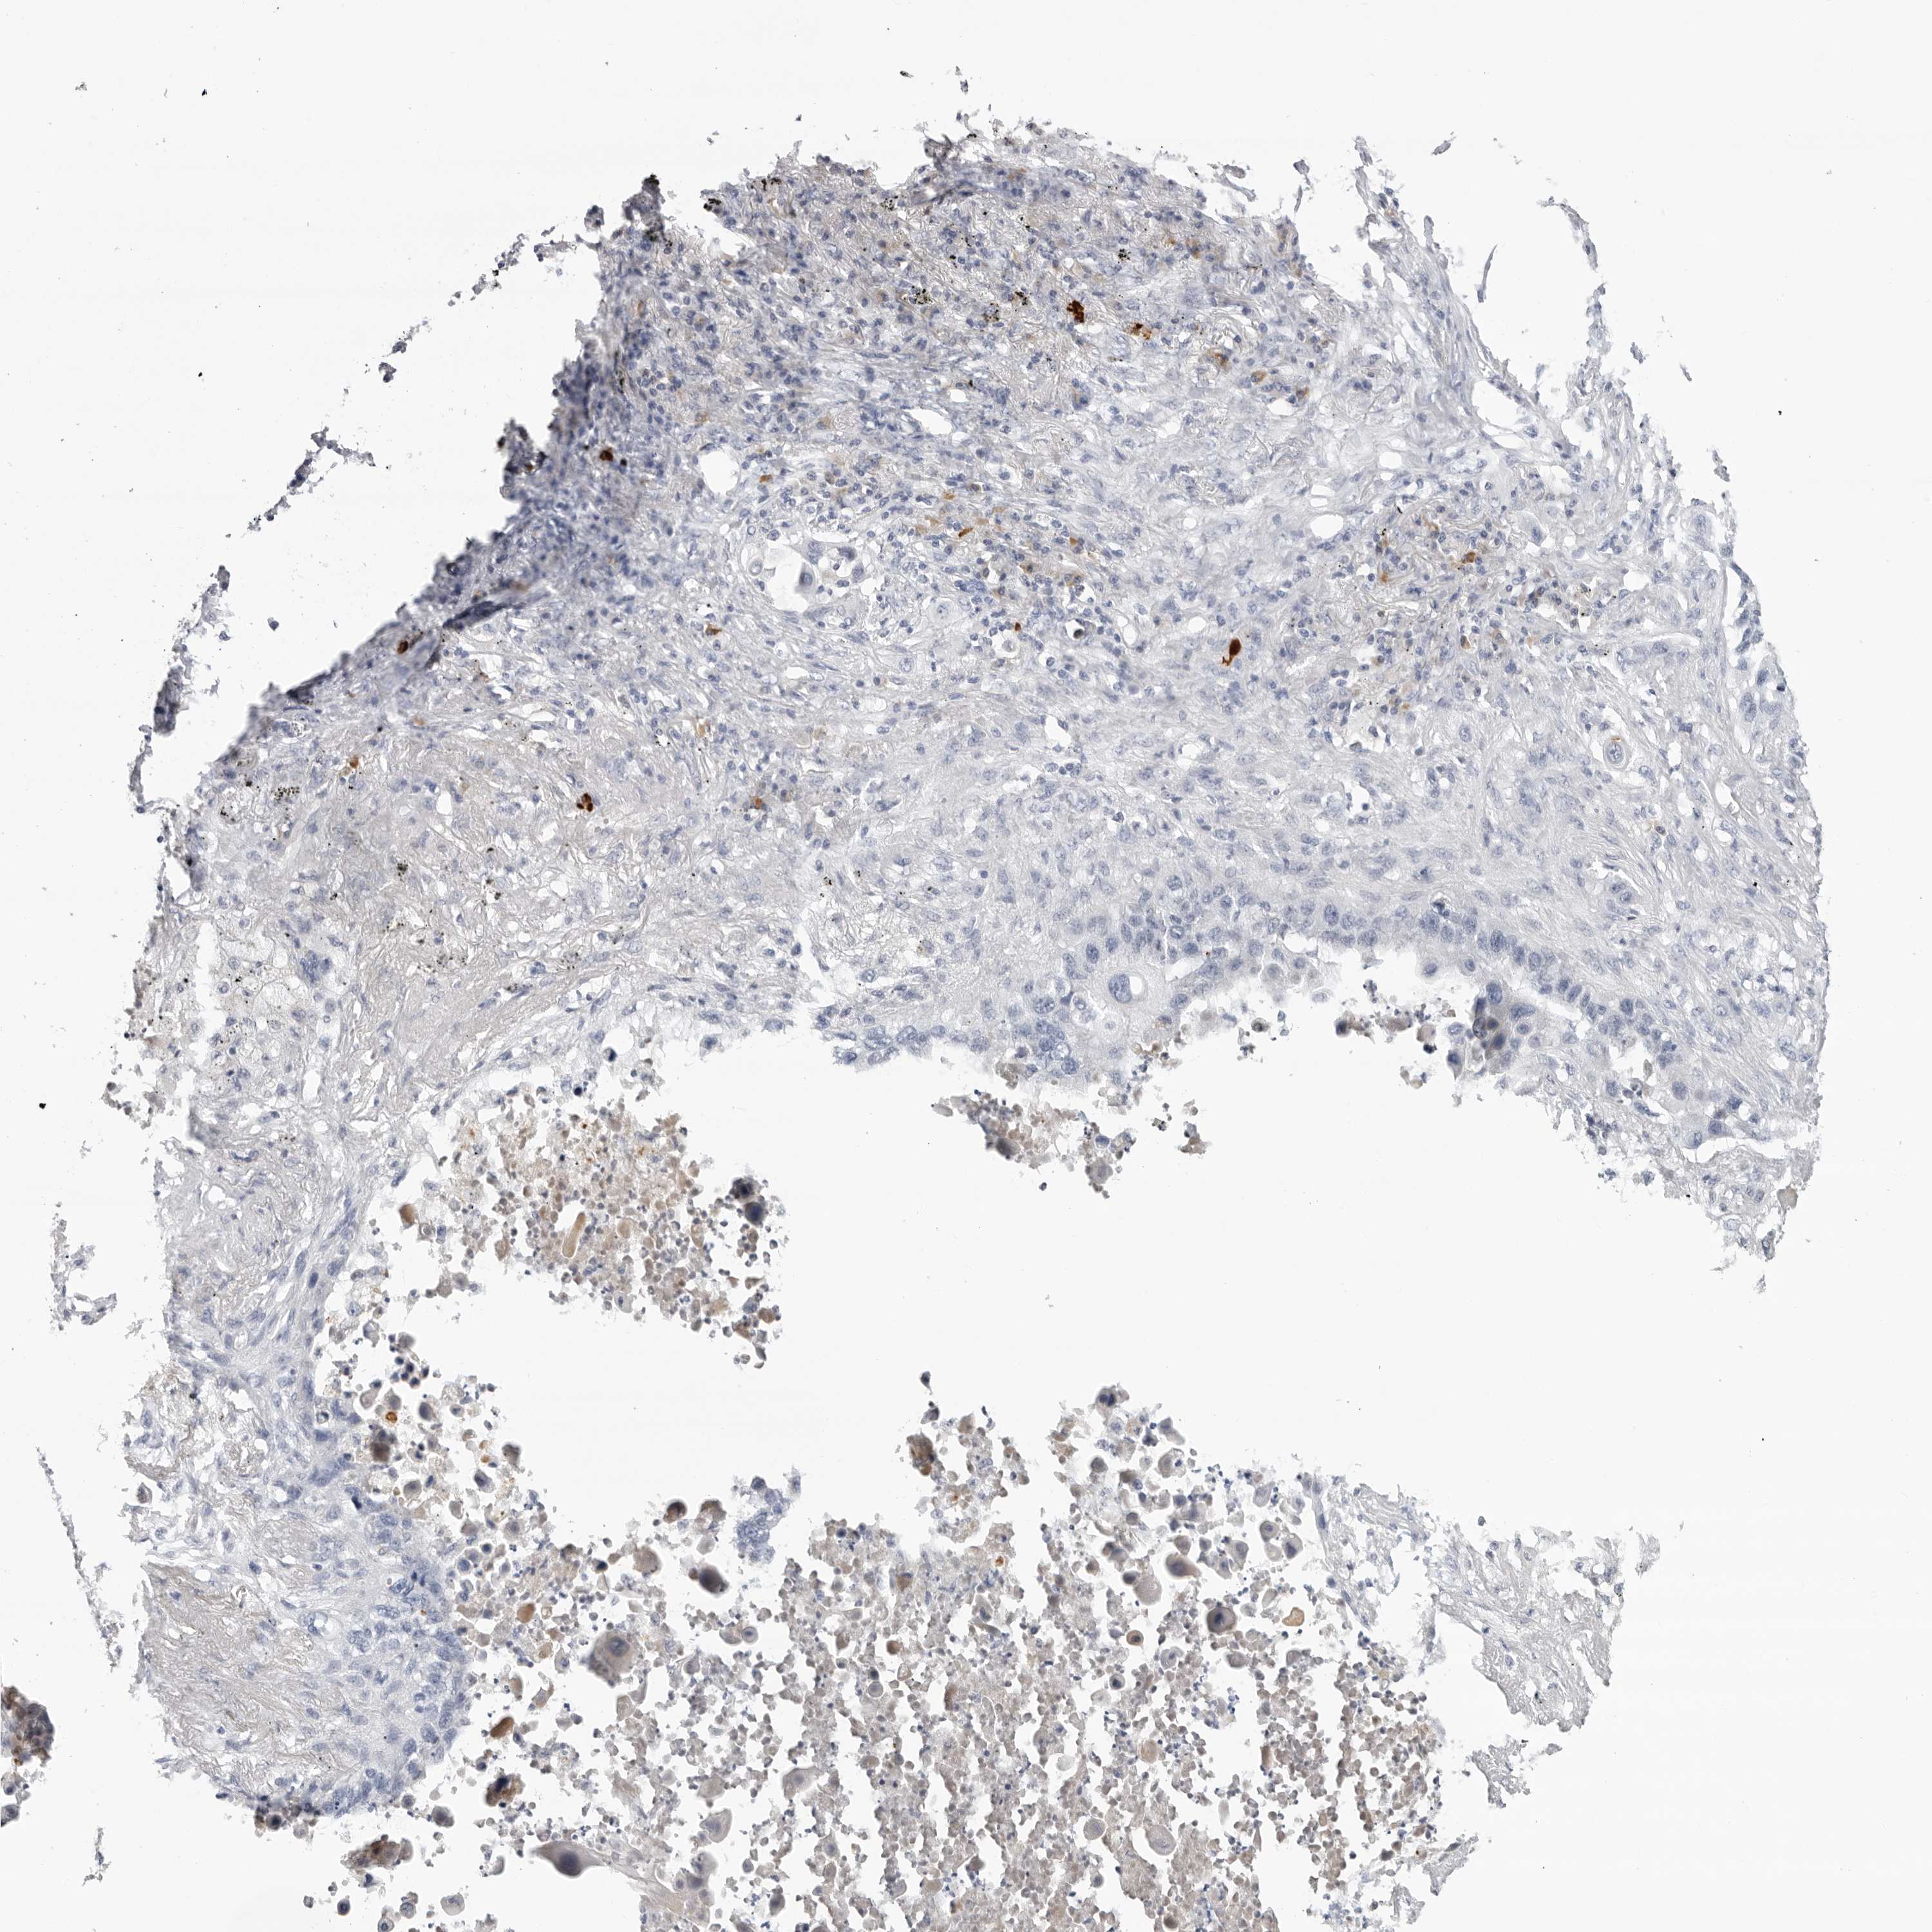

LUNG ADENOCARCINOMA (VALIDATION) - Interactive survival scatter ploti

The Survival Scatter plot shows the clinical status (i.e. dead or alive) for all individuals in the patient cohort, based on the same data that underlies the corresponding Kaplan-Meier plots. Patients that are alive at last time for follow-up are shown in blue and patients who have died during the study are shown in red.

The x-axis shows the expression levels (FPKM) of the investigated gene in the tumor tissue at the time of diagnosis. The y-axis shows the follow-up time after diagnosis (years). Both axes are complimented with kernel density curves demonstrating the data density over the axes. The top density plot shows the expression levels (FPKM) distribution among dead (red) and alive patients (blue). The right density plot shows the data density of the survived years of dead patients with high and low expression levels respectively, stratified using the cutoff indicated by the vertical dashed line through the Survival Scatter plot. This cutoff is automatically defined based on the FPKM cutoff that minimizes the p-score. The cutoff can be changed by dragging the vertical line or by entering a cutoff value in the square labeled "Current cut-off".

Under the Survival Scatter plot the p-score landscape (black curve; left axis) is shown together with dead median separation (red curve; right axis). Dead median separation is the difference in median mRNA expression between patients who have died with high and low expression, respectively. It is calculated as follows: median FPKM expression of dead patients with high expression - median FPKM expression of dead patients with low expression. This is intended to aid the user in visually exploring custom cutoffs and the associated p-scores and dead median separation.

Individual patient data is displayed and can be filtered by clicking on one or more of the category buttons on the top of the page. Categories describing expression level and patient information include: high, low, alive, dead, female, male and tumor stages. The scale of the x-axis can be toggled between linear and log-scale by clicking on the "x log" button. Mouse-over function shows TCGA ID, patient information and mRNA expression (FPKM) for each patient.

& Survival analysisi

Kaplan-Meier plots summarize results from analysis of correlation between mRNA expression level and patient survival. Patients were divided based on level of expression into one of the two groups "low" (under cut off) or "high" (over cut off). X-axis shows time for survival (years) and y-axis shows the probability of survival, where 1.0 corresponds to 100 percent.

ZNF502 is not prognostic in Lung Adenocarcinoma (validation)

: 1.48

Average pTPM 1.9

Number of samples 105